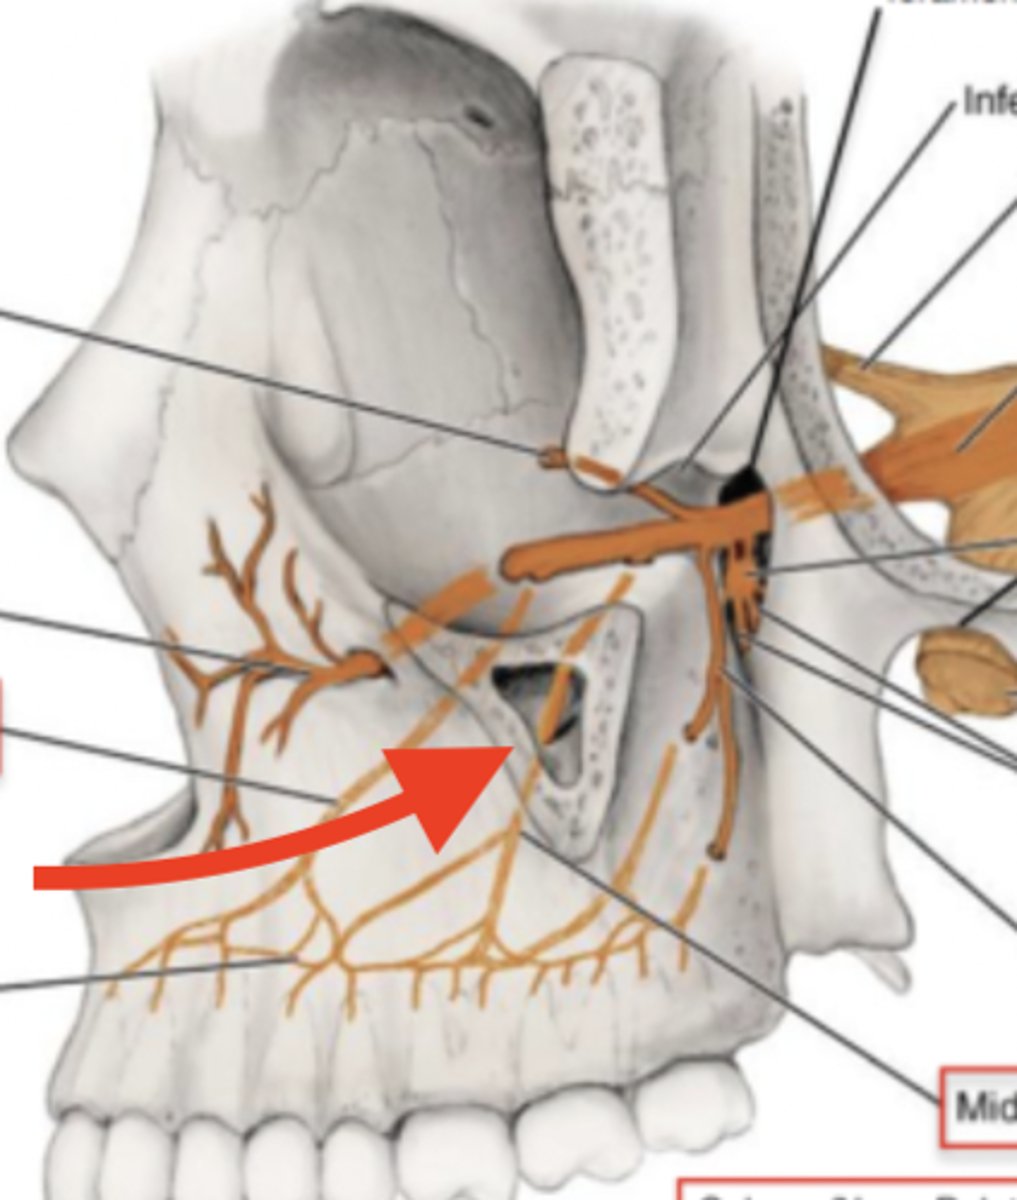

infraorbital foramen of maxilla

anterior nasal spine of maxilla

maxillary sinus of maxilla

lacrimal groove of maxilla